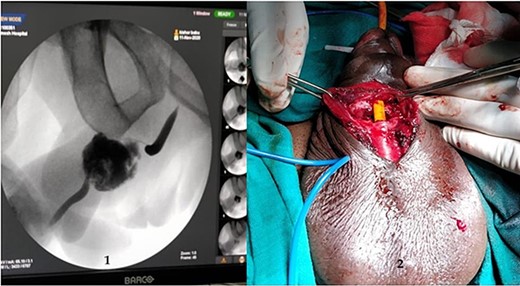

A 37-year-old male presented with a history of a ‘snap’ sound and immediate detumescence of penis during intercourse, when he fell and hit the pubic bone of his partner. There was generalized swelling and pain in the penis. There was acute retention of urine, an attempt to pass a catheter failed and the patient underwent supra-pubic catheterization. On examination, there was classical ‘eggplant deformity’ of the penis with blood at the tip of the meatus. MRI showed a tunical tear on both sides at the penoscrotal junction with indistinct urethra and extensive hematoma in the proximal penile shaft (Fig. 1). With the diagnosis of a fractured penis and possible urethral injury, after proper counselling, the patient was taken up for surgery. On the table, a retrograde urethrogram (RGU) was done showing evidence of partial urethral disruption. On exploration with penoscrotal vertical incision, there was total transection of proximal penile urethra, and a 1.5 cm tunical injury of corpus cavernosum on both sides ventrally (Fig. 2). There was extensive hematoma. Corpora sutured with 4.0 prolene after reconstructing the midline septum. Urethral ends mobilized and anastomosed with 3.0 vicryl in a single layer with minimal spatulation (Fig. 3). The patient was discharged on the 5th post-operative day; Foley catheter was removed on day 21. Follow-up RGU done after 3 months showed no evidence of stricture (Fig. 4).

An MRI with (1) left corporeal tear on the left side with surrounding hematoma and (2) right corporeal tear with hematoma and disruption of urethra.

(1) On table RGU showing evidence of partial urethral disruption and (2) total transection of proximal urethra on exploration with penoscrotal vertical incision.